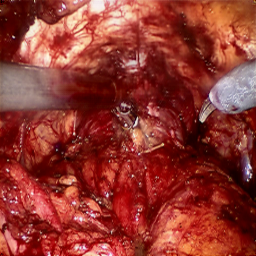

Refer to caption (a) Input Refer to caption (b) DIACMPN Refer to caption (c) Desmoke-LAP Refer to caption (d) PFAN Refer to caption (e) MITNET Refer to caption (f) Salazar Refer to caption (g) Dehamer Refer to caption (h) Ours Refer to caption (i) Target

Figure 2: Comparison of different methods on the DesmokeData dataset.

IV-C2 Qualitative Analysis

Figures 3 and 2 provide a visual comparison of the desmoking results on challenging images from the test sets. The visual results corroborate our quantitative findings. DCP not only fails to remove the dense smoke but also introduces severe color distortion. CNN-based methods like FFA-Net and MSBDN successfully remove a large portion of the smoke but tend to either leave behind a thin layer of residual haze or over-smooth the image, losing critical textural details of the tissue and surgical instruments. The Transformer-based methods, DehazeFormer and PFAN, produce significantly better results by restoring more details. However, they can sometimes struggle with non-uniform smoke distribution, resulting in regions with unnatural brightness or minor artifacts.

In stark contrast, our RGA-Net generates visually superior results that are remarkably close to the ground-truth images. It effectively removes even the densest plumes of smoke while simultaneously preserving fine-grained details, such as blood vessels, tissue textures, and reflections on surgical tools. Furthermore, the color and illumination of the restored scene appear more natural and consistent, which is a direct benefit of our model’s ability to handle both local and global features through its hybrid attention and cross-gating mechanisms. This enhanced visual clarity is crucial for improving the surgeon-robot interface in real-world clinical applications.